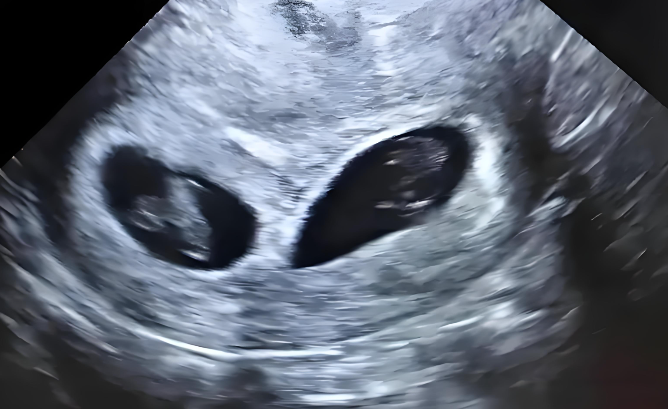

在孕期交流中,常能听到关于“孕囊形状判断胎儿性别”的说法,不少准爸妈将其视为“民间智慧”,甚至当作提前知晓宝宝性别的线索。但医学真相却与这种流传大相径庭, 孕囊形状与胎儿性别毫无关联 ,这一认知误区可能误导对孕期健康的关注方向。

二、孕囊形状的真相

临床观察发现,孕囊形状千差万别,可呈圆形、长条形、不规则形等,但这些差异并非由胎儿性别决定,而是受以下客观因素影响:

超声检查角度 超声探头与子宫的相对位置会改变成像视角。若探头倾斜,圆形孕囊可能被投影为长条形,类似“侧看圆柱变扁条”。

子宫形态与位置 子宫前倾、后倾或存在先天畸形(如双角子宫)时,孕囊为适应宫腔形态会呈现不同形状,与胎儿性别无关。

孕囊发育阶段 孕囊早期较小(直径<1厘米)时,形态易受周围积液或组织挤压变形;随着孕周增加(约7周后),会逐渐被胚胎及羊膜囊撑开,形状趋于规则。

测量误差 超声测量受设备精度、操作者经验影响,同一孕囊不同切面测量的长径、短径可能有细微差异,导致形状描述偏差。

由此可见, 孕囊形状是多种客观因素共同作用的结果,与胎儿染色体(决定性别的关键)无任何联系 。目前没有任何临床研究证实,孕囊长宽比或其他形态特征能预测胎儿性别。